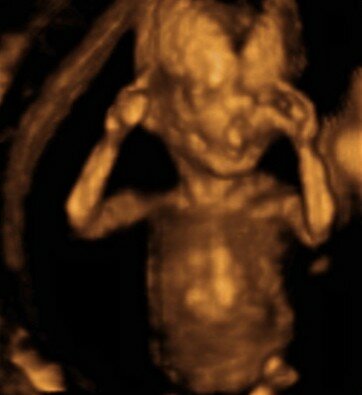

• Funcionamiento de sus órganos (Semana 24)

Funcionamiento de sus órganos (Semana 24)

Los sigue perfeccionando y puede escuchar los ruidos del exterior y la voz de su madre y las personas que la acompañan